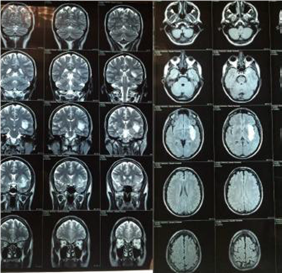

Paciente de sexo masculino, 58 años, 180 cm de altura, peso de 78 Kg, coordinado para resección de lesión temporoinsular izquierda (Figura 1).

Figura 1: Tomografía de la lesión cerebral.